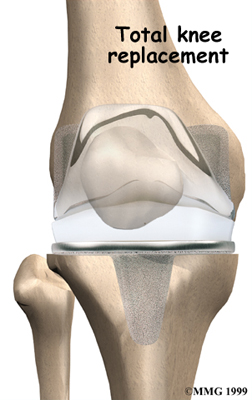

Artificial Knee Replacement

An artificial knee replacement is the ultimate solution for advanced knee OA.

Surgeons prefer not to put a new knee joint in patients younger than 60. This is because younger patients are generally more active and might put too much stress on the joint, causing it to loosen or even crack. A revision surgery to replace a damaged prosthesis is harder to do, has more possible complications, and is usually less successful than a first-time joint replacement surgery.

Related Document: FYZICAL South Frederick's Guide to Artificial Joint Replacement of the Knee